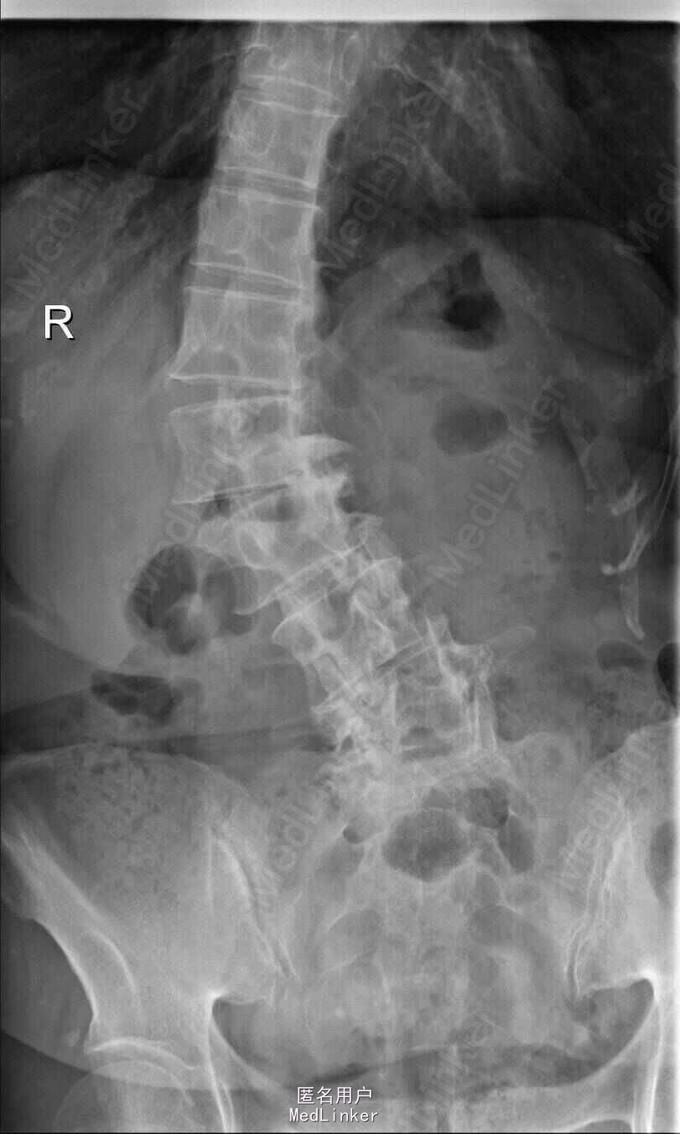

查体:脊柱侧弯,上肢无麻木,疼痛感觉异常,腰部右侧疼痛,右下肢及右臀部疼痛,麻木感。双侧肌力及肌张力可,膝腱反射(+),踝反射(+),病理征(—),直腿抬高试验。右侧40度,左侧55度。 辅助检查:腰椎x线片:腰椎侧弯,腰椎退行性改变,L5椎体略行前滑脱 脊柱全长:胸腰段呈S形,L5椎体向前滑脱,L3椎体略变扁,颈胸腰椎退行性改变 MRI:脊柱侧弯,L2-3,L3-L4,L4-L5,L5-S1椎间盘突出,相应节段椎管狭窄

诊断:腰椎侧弯,腰椎椎管狭窄 治疗:手术矫形:早期侧路减压融合,后期再行后路固定。

随访:病人初期手术时间段,术后恢复较快,病人神经压迫症状解除,腰部侧弯获得一定程度的矫正,术后起床用支局支撑后,可以下床活动,后期手术行后路经皮内固定。